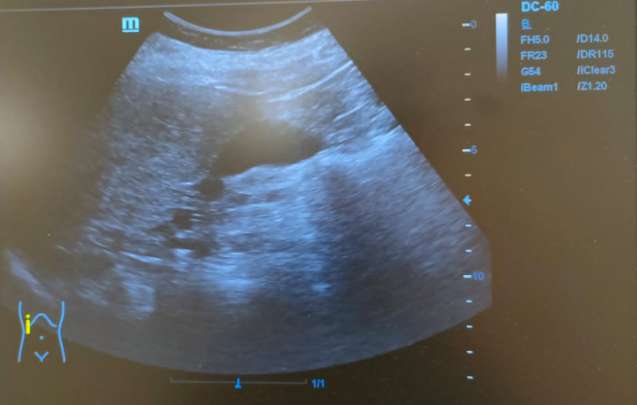

Hígado de tamaño normal, contornos ligeramente nodulares, alteración de la ecoestructura compatible con hepatopatía crónica. Nódulo hipoecoico de contornos irregulares en lóbulo hepático izquierdo de 16x24mm sin captación Doppler.

Tras realizar la ecografía en el CAP se observó un nódulo hipoecoico de contornos irregulares. Entre los diagnósticos diferenciales posibles que justificasen el patrón de colestasis se encontraba el CHC o una metástasis, por lo que se realizó una prueba complementaria que confirmó el diagnóstico de CHC.